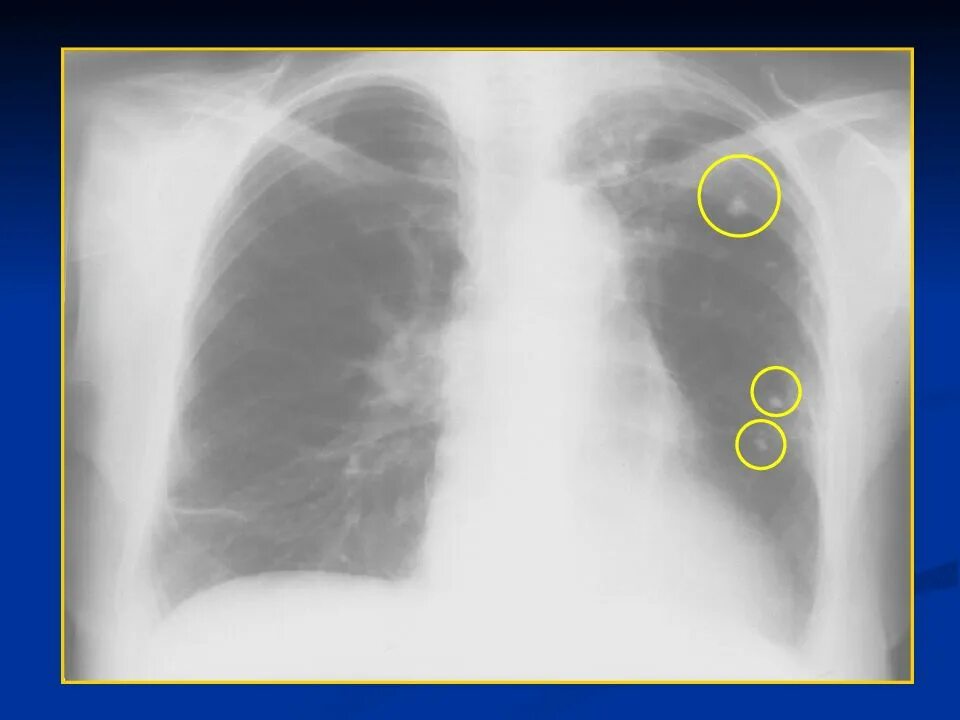

Бронхоаденит это